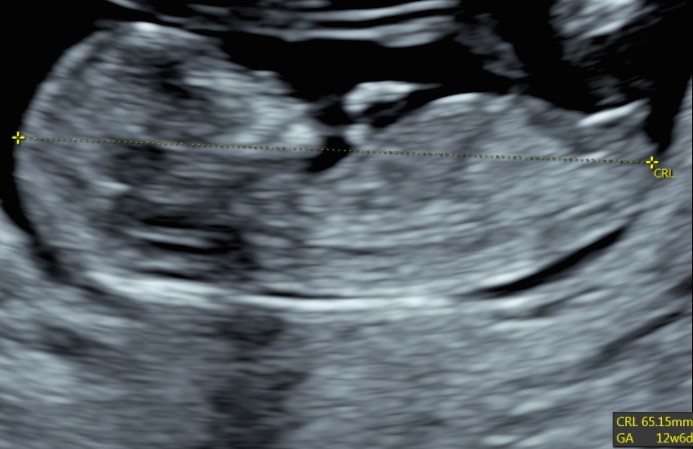

Indipendentemente dalla nostra scelta, è di capitale importanza fare comunque una ecografia fra la 11° e la 13° settimana. Infatti già a questa epoca gestazionale siamo in grado di condurre un’iniziale valutazione morfologica. Ma soprattutto questo è la finestra di opportunità per studiare la translucenza nucale. In realtà questa ampia finestra di tre settimane ha il suo momento più favorevole a 11 settimane e mezza e inizio dodicesima.

Si va a misurare quindi attraverso una ecografia lo spazio dietro la nuca: è una fisiologica raccolta di linfa che tende ad aumentare in diverse situazioni patologiche risultando essere un indice generale di buon andamento della gravidanza dove più è sottile più siamo tranquilli a riguardo di patologie cromosomiche, malformazioni cardiache, ed alcune malattie genetiche.

| Translucenza nucale | |||

| CRL (mm) | 5° percentile | 50° percentile | 95° percentile |

| 40 | 0.31 | 1.22 | 2.14 |

| 45 | 0.40 | 1.32 | 2.24 |

| 50 | 0.50 | 1.42 | 2.34 |

| 55 | 0.60 | 1.52 | 2.44 |

| 60 | 0.70 | 1.62 | 2.54 |

| 65 | 0.80 | 1.72 | 2.64 |

| 70 | 0.90 | 1.82 | 2.73 |

| 75 | 0.99 | 1.91 | 2.83 |

| 80 | 1.09 | 2.01 | 2.93 |

| 85 | 1.19 | 2.11 | 3.03 |